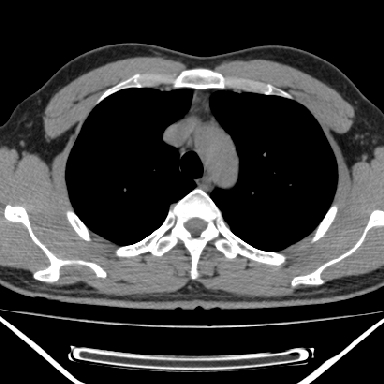

m 30 右胸痛10年

右上后纵隔脊柱旁类圆形肿块,边界光整,与胸腔呈钝角,首先考虑来源于肺外,神经源性肿瘤(神经鞘瘤可能大,神经鞘瘤)

右上后纵隔旁软组织肿块影,与肺界面光滑,与胸壁呈钝角相交,提示肺外病变。位于肋骨下缘,边缘清楚,呈三角样指向与右侧椎间孔,但并示进入椎间孔;与对侧神经根对比,属同一走行方向。

考虑后纵膈良性肿瘤,神经源性肿瘤可能大。

鉴别:胸膜来源肿瘤。影像表现虽有肺外征象,但无胸水等相应佐证;再者,病史前10年,超长,与胸膜肿瘤不太吻合。

右上后纵隔脊柱旁类圆形肿块,边界光整,与胸腔呈钝角,首先考虑来源于纵膈,神经源性肿瘤可能大。

右上后纵隔脊柱旁见长椭圆形肿块,边界光整,与胸壁呈钝角。周围骨质未见异常。

考虑、1、后纵隔神经源性肿瘤;

2、不除外单发胸膜间皮瘤。